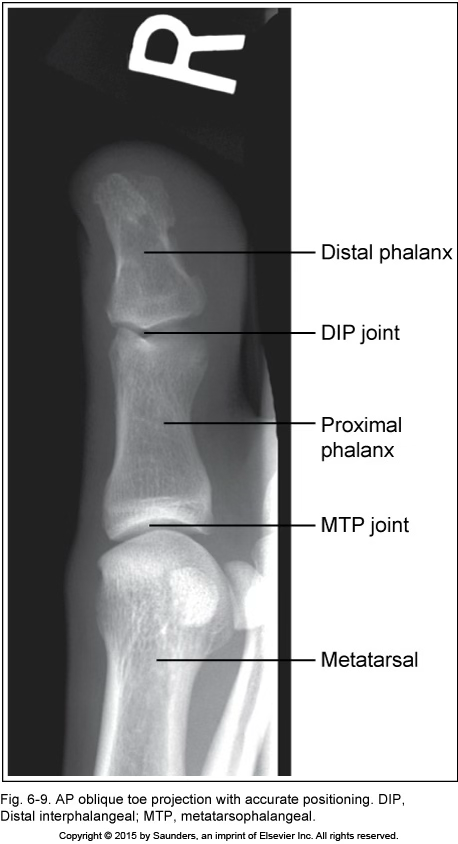

AP oblique toe

accurate positioning